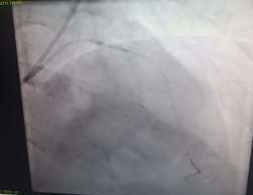

60 year old male known diabetic, hypertensive and dyslipidaemic presented with unstable angina, Coronary angiogram revealed Mid RCA pre crux lesion of 80-90% stenosis and PDA and PLV arising from Mid RCA (Fig 1). It was an angulated bend post bifurcation and hence Fielder FC wire support was taken to easily manipulate the vascular bifurcation (Fig 2) and successful PTCA+ stent to Mid RCA was done with 3x24mm Yukon choice flex stent (Fig 3& 4). TIMI III flow was achieved and post procedure period was uneventful.

FIG 4: Final Shot